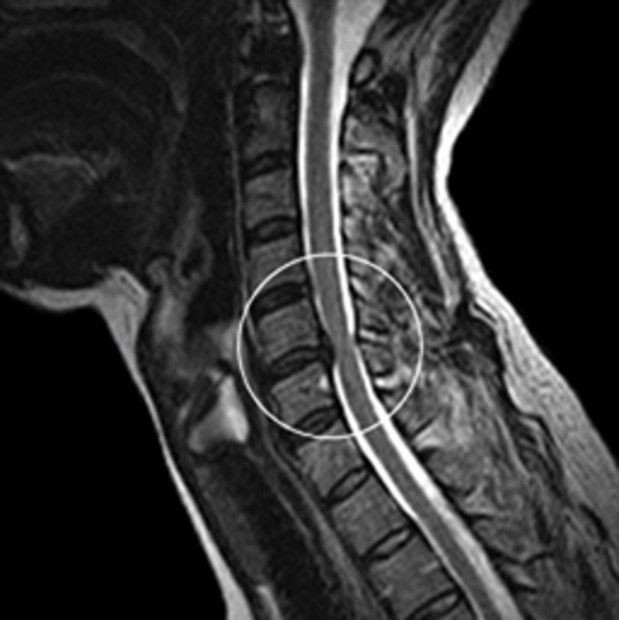

오늘은 목 건강을 위협하는 질환, **목디스크(경추 추간판 탈출증)**의 증상에 대해 이야기하려 합니다. 목디스크는 목뼈 사이에 있는 디스크가 제자리를 벗어나 신경을 압박하면서 발생하는 질환입니다.

- 설명: 목디스크가 심하게 진행되어 척수를 압박하면 하체까지 증상이 나타날 수 있습니다. 다리에 힘이 빠지고, 보행이 불안정해지며, 심한 경우 마비 증상이 나타나기도 합니다. 이는 즉시 치료가 필요한 심각한 합병증입니다.